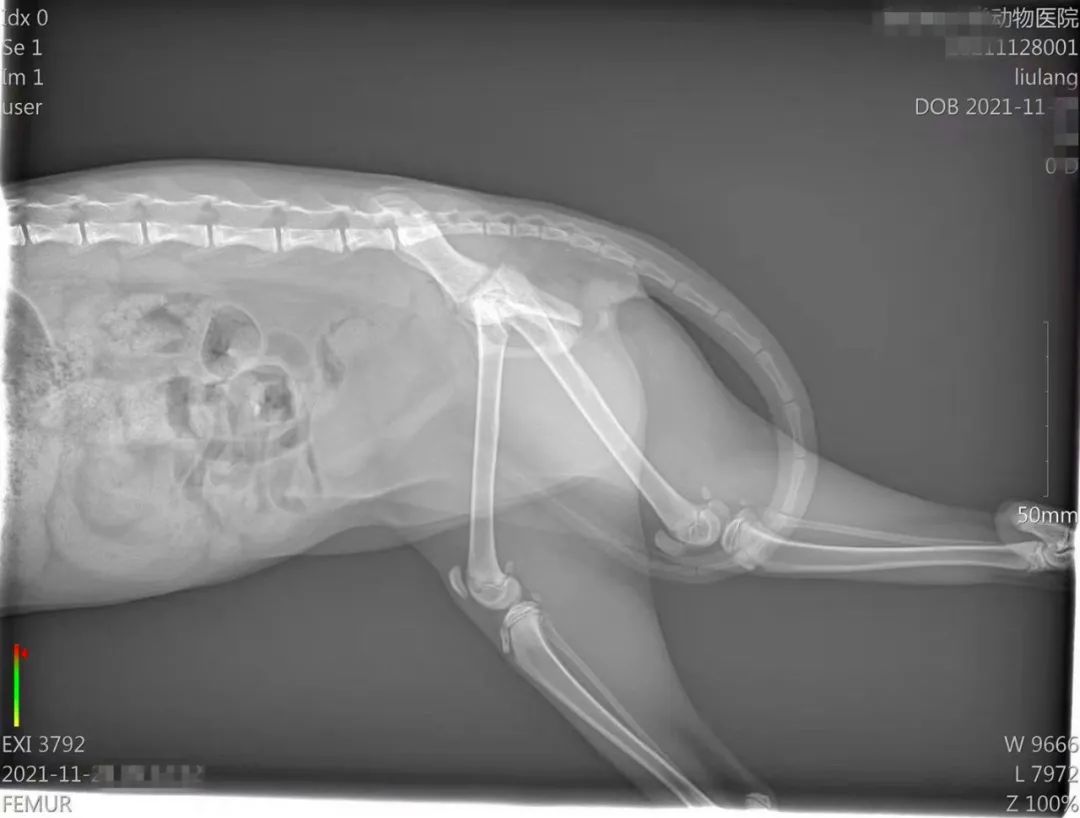

上午8點(diǎn),小瑞將受傷的貓咪送至最近的寵物醫(yī)院,經(jīng)過拍片確診,貓咪腿骨骨折,必須馬上手術(shù),需要6000元的手術(shù)費(fèi)。

圖片

醫(yī)院拍片顯示,貓咪腿骨骨折

而丁嬌則把消息轉(zhuǎn)發(fā)至更多業(yè)主群以及救助群,并重新聯(lián)系了一家寵物救助醫(yī)院!敖(jīng)過細(xì)致檢查,貓咪不僅骨折,還伴有膈疝,就是胸腔膈肌破裂,肝臟進(jìn)入胸腔壓迫肺,導(dǎo)致呼吸困難。”